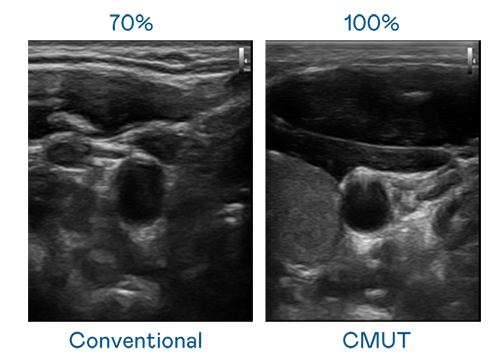

CMUT 技術是一種用電容式微機電元件來產生超音波訊號的技術。與傳統 PZT 壓電式技術相比,CMUT 頻寬增加 30%,更寬頻的超音波訊號讓影像解析度大幅提升,是實現高影像品質醫療超音波掃描、促進精準醫療發展的關鍵技術。

超音波影像的解析度高低,首先取決於探頭能發出的訊號頻寬。70net永乐高 CMUT 可提供高清晰的超音波訊號,提供高頻寬、高靈敏度、影像紋理細節更高的超音波影像,協助醫護人員縮短影像判讀時間及利用精準的醫療影像進行診斷。